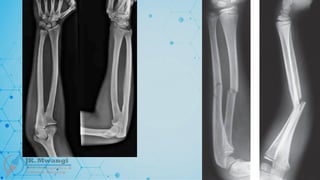

Galeazzi fracture

 A fracture of the radius with associated dislocation of the distal radioulnar joint

(DRUJ). Named after Ricardo Galeazzi, who described it in 1934

Monteggia fracture

 A fracture of the proximal third of the ulna with dislocation of the radial head.

Named after Giovanni Battista Monteggia in 1814